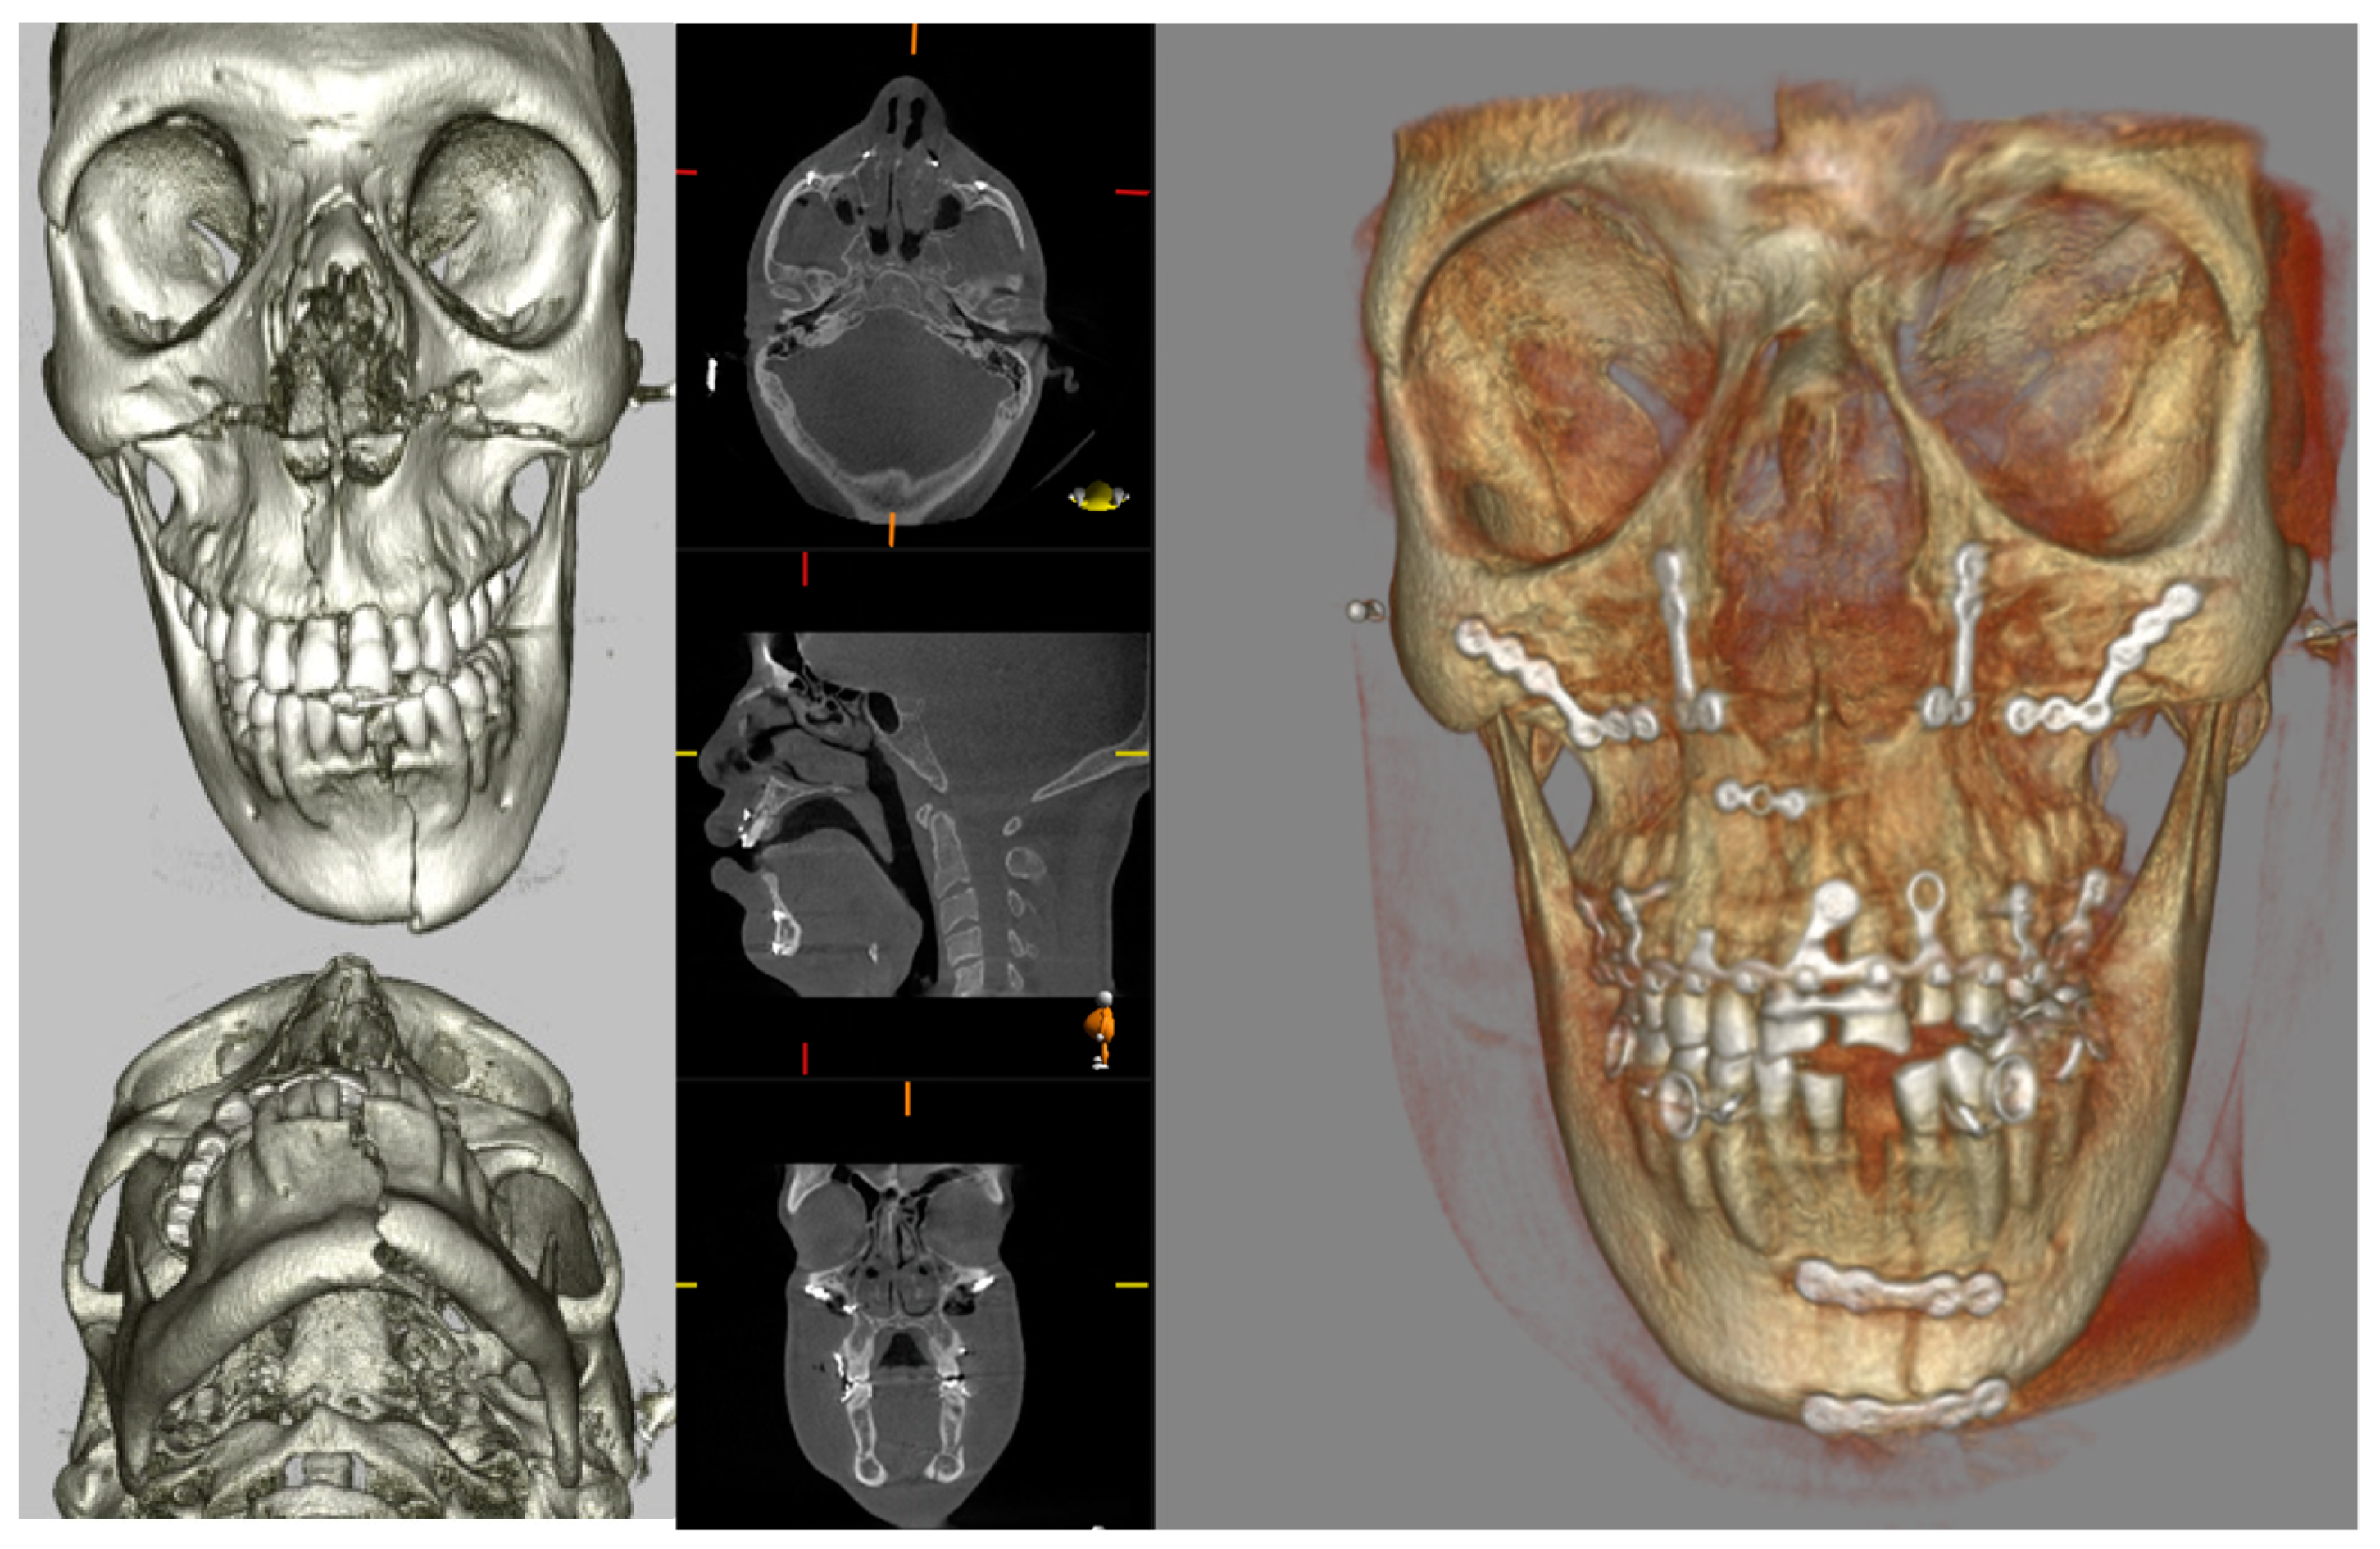

Similarly, midface fractures comprising a Le Fort Pattern are best appreciated with cross-sectional imaging. These fractures often accompany a multi-injured patient, and thus conventional CT is more readily utilised in non-ambulatory and comorbid patients. Otherwise, CBCT can show a larger number of fracture lines and fragments [40], and 3D printing can facilitate surgical planning, the alignment of teeth, and the construction of custom arch bars without the need for impressions. In our unit, CBCT is often utilised to assess fracture reduction post fixation (Figure 7). This serves as a baseline post-operative image and a more reliable assessment of bone reduction than a plain X-ray.

Figure 7.

Pre-operative CT 3D volume renders and post-operative CBCT axial, sagittal, coronal slices, and 3D volume render showing reduction and fixation of fractures through the symphysis mandible, Le Fort 1 level, and maxillary alveolar bone.